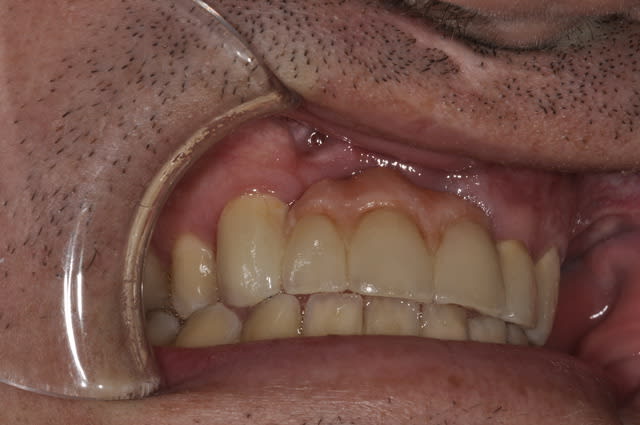

Bridge sur patient ayant une fente faciale.

J'ai du déposé le bridge ailette et faire l'extraction de 11 et 21 pour cause resorption externe.

Puis bridge sur dent vivante avec 13/22/23 comme pilier.

J'ai revu le patient au bout d'un an.

Hygiéne approximative mais pas évidente en même temps.

Je vous ai mis des photos du labo, puis 1 semaine après la pause et enfin celles de la semaine dernière.

On constate des petites zones inflammatoires au niveau des piliers et une légére perte d'attache sur la 23.

Photo prise juste après le détartrage, mais n'excuse pas tous.